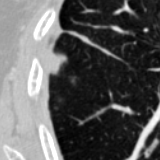

The current study focuses on lung nodule retrieval from a database of CT scans, where patches taken from CT slices of pulmonary nodules are to be mapped into an embedding. LIDC-IDRI [5] is a dataset of thoracic CT scans of 1,010 patients. All the scans were annotated by up to four radiologists, where each one identified, segmented and evaluated separately the lung nodules of a diameter above . Their evaluation also included ratings for a set of 9 characteristics: Subtlety, Internal structure, Calcification, Sphericity, Margin, Lobulation, Spiculation, Texture and Malignancy. The rating system was based on a discrete score of 1-5. Four examples of nodule patches are illustrated in Figure 2: 2 benign (a, b) and 2 malignant (c, d). A rounded vector of the mean rating is bellow each nodule, with the characteristics ordered according to the listing above. The most prominent difference between a and b is the calcification: 3 (solid) and 6 (absent) accordingly. d compared to c has a more defined margin, is more lobulated, but less spiculated. The malignancy score is used to define malignancy classes: score of 1-2 is benign, score of 3 is unknown, and a score of 4-5 is malignant.

(a) Benign

3, 1, 3, 3, 4, 3, 1, 5, 1

(b) Benign

3, 1, 6, 5, 5, 1, 1, 5, 2

(c) Malignant

5, 1, 6, 3, 3, 4, 1, 5, 5

(d) Malignant

4, 1, 6, 3, 4, 2, 2, 5, 4